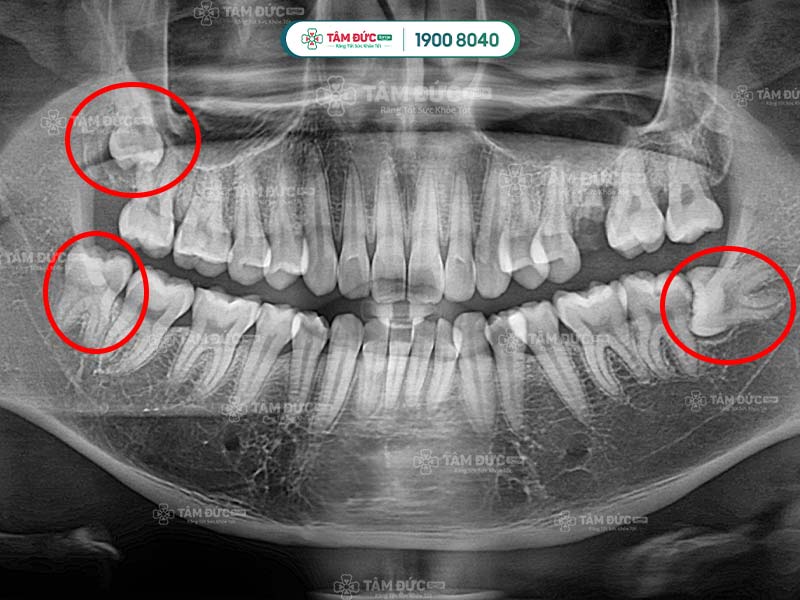

Dấu hiệu nhận biết Quý khách có răng khôn mọc lệch 45 độ là các cơn đau âm ỉ, kéo dài nhiều ngày. Nguyên nhân là vì khoảng trống trên hàm đã không còn nhiều, vị trí của răng khôn bị ảnh hưởng bởi mô mềm và răng hàm số 7. Điều này đã làm răng mọc nghiêng theo nhiều góc độ so với răng số 7 như 45 độ hay 90 độ.

Bước 2: Đối với răng khôn mọc lệch, Quý khách cần được chụp X-Quang để xác định hướng mọc, vị trí của chân răng, xương hàm và dây thần kinh.